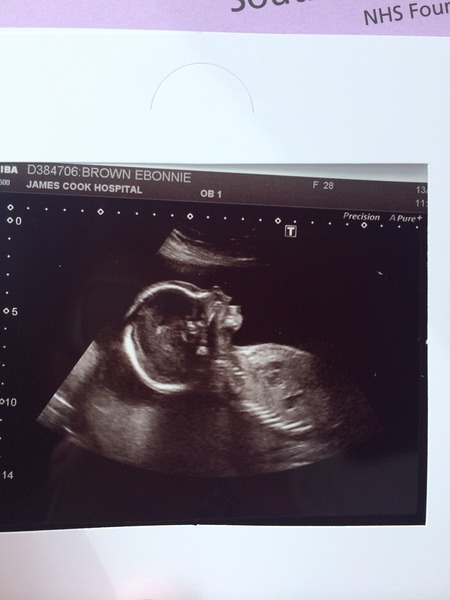

Mrseb what an amazing scan picture: one of the clearest I've ever seen. Your hospital must have high tech equipment and/ or great sonographers!

What a lovely scan pic!